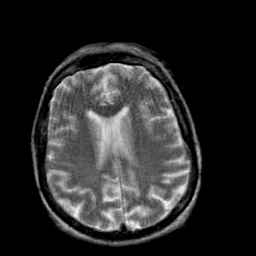

Creutzfeld-Jakob disease: T2-weighted MR -- Slice #15

[Home][Help][Clinical] Slice 15